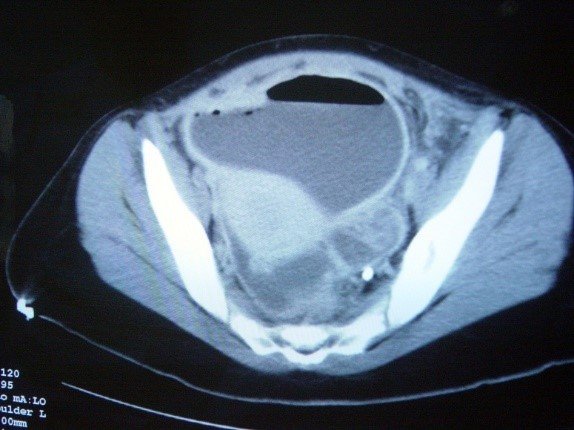

- KT yüksək həssaslıq və spesifiklik (95%) göstərir, diaqnostik çətinlikdə istifadə edilir. Genişlənmiş (diametri 6 mm-dən çox), divarı qalınlaşmış appendiks, ətrafında ödem, abses, fleqmona kimi əlamətlər appendisitə xarakterikdir (Şəkil 2).

Şəkil 2. Appendisitin diaqnostikası